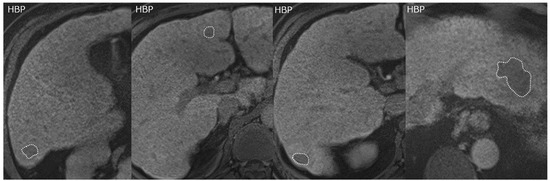

- Fujita, N.; Nishie, A.; Kubo, Y.; Asayama, Y.; Ushijima, Y.; Takayama, Y.; Moirta, K.; Shirabe, K.; Aishima, S.; Honda, H. Hepatocellular carcinoma: Clinical significance of signal heterogeneity in the hepatobiliary phase of gadoxetic acid-enhanced MR imaging. Eur. Radiol. 2015, 25, 211–220. [Google Scholar] [CrossRef]